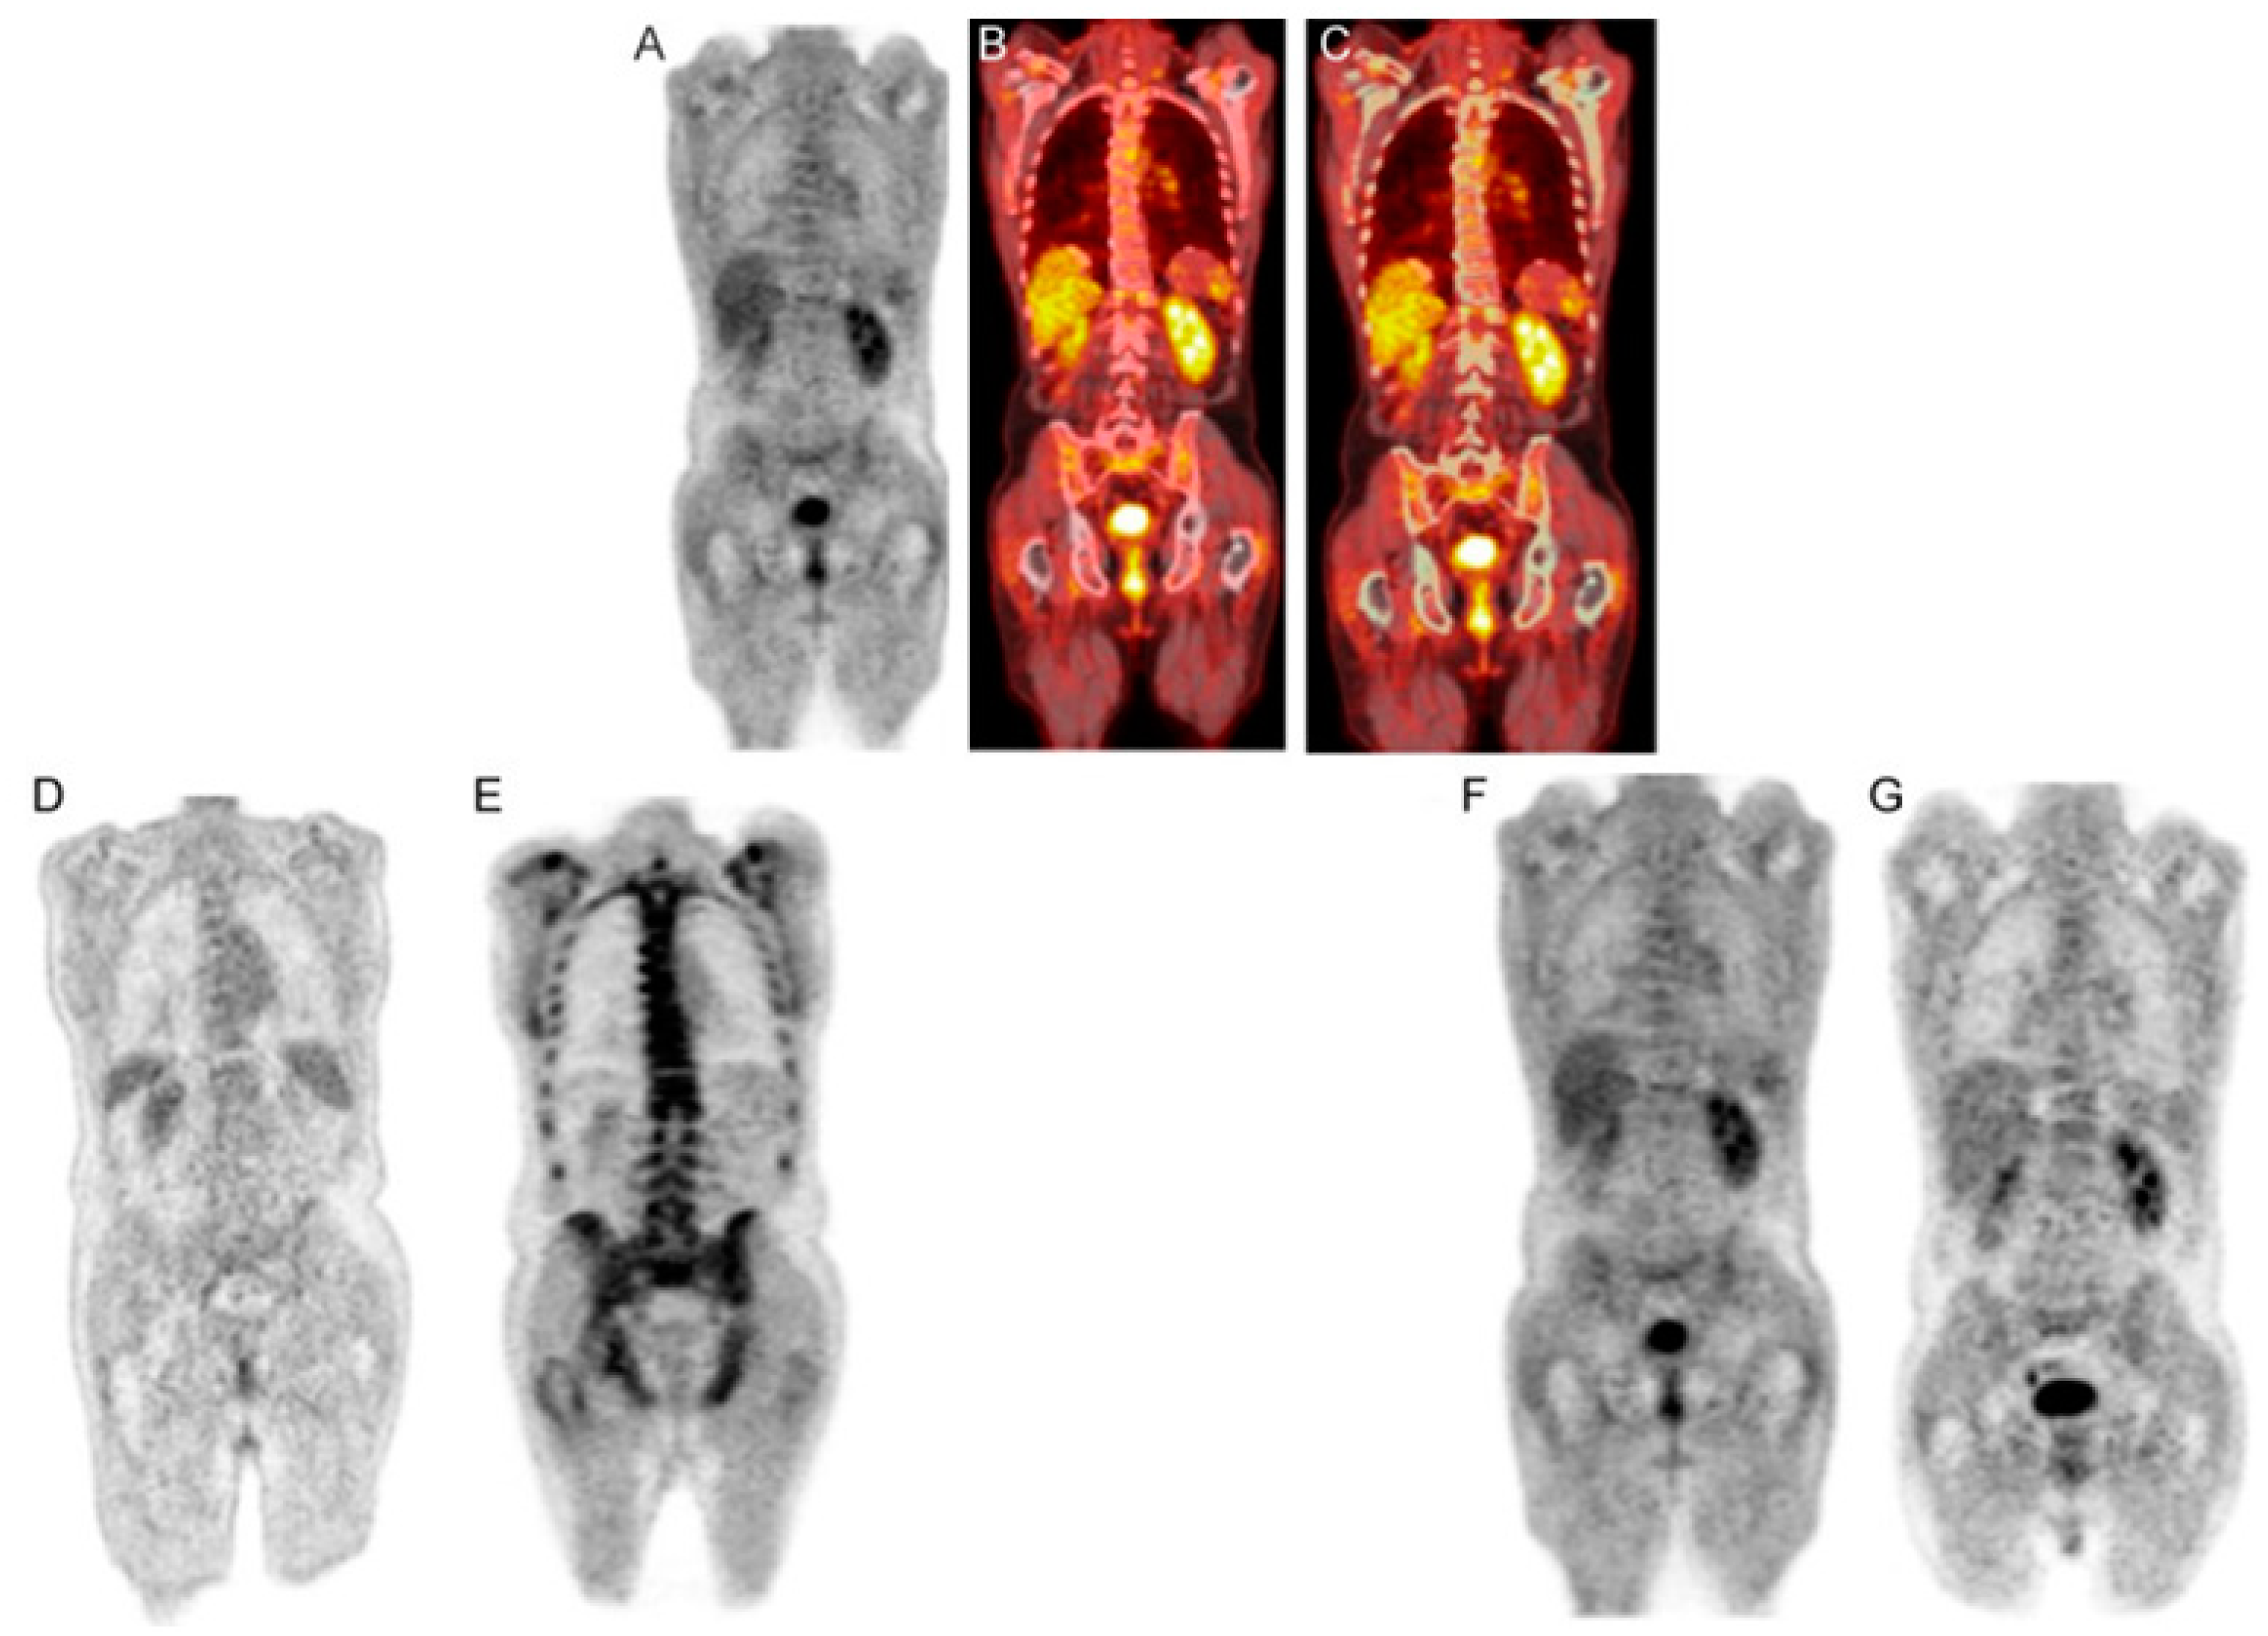

11. Italian Myeloma Criteria for Pet Use: IMPeTUs

A team of Italian researchers has proposed an extensive set of PET criteria, IMPeTUs, for evaluating myeloma (Figure 13) [51]. The ambit of the IMPeTUs approach encompasses the assessment of the intensity of osteolytic bone disease and the quantification of metabolic activity within the bone marrow, extramedullary regions, and paramedullary areas (Figure 13) [51]. Moreover, this method includes the ranking of the top three significant focal lesions in the body. IMPeTUs appears to cover essential and separate risk factors in myeloma [51]. However, the detection of these aspects visually is dependent on the observer’s proficiency and expertise [49]. The lack of substantial experience among junior radiologists and nuclear medicine physicians could potentially undermine the repeatability and consistency of this approach [49]. Despite this obstacle, the authors were able to show a positive consensus in the interpretation of results, with a minimum rate of 75% for bone marrow (BM), 76% for the focal score, 95% for extramedullary disease, 76% for the tally of focal lesions, 77% for the number of lytic lesions, and 92% for the detection of fractures [51].

Figure 13.

IMPeTUs. (A) Maximum intensity projection (MIP); (B) sagittal cut of the PET scan; (C) sagittal cut of the CT scan. This shows a widespread and intense bone marrow uptake in the limbs, pelvis, and spine. This patient exhibits diffused enhanced bone marrow uptake, which also involves the limbs, with a fracture in T10 (the tenth thoracic vertebra). In this case, the Identified Myeloma PET Uptake Score (IMPeTUs) is BM4 A (indicating increased bone marrow uptake extending into the limbs) and Fr (one fracture identified on CT scan), Cancers 2020, 12(4), 1030; https://doi.org/10.3390/cancers12041030, OPEN ACCESS [52].